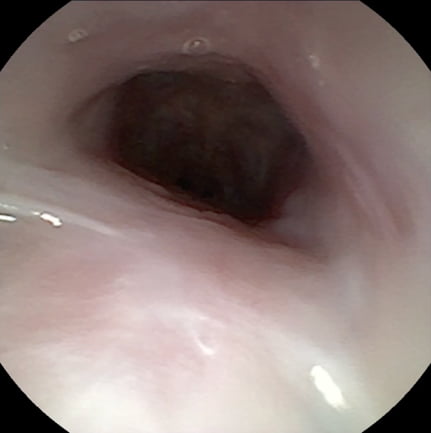

鼻咽頭狭窄の治療前と治療後